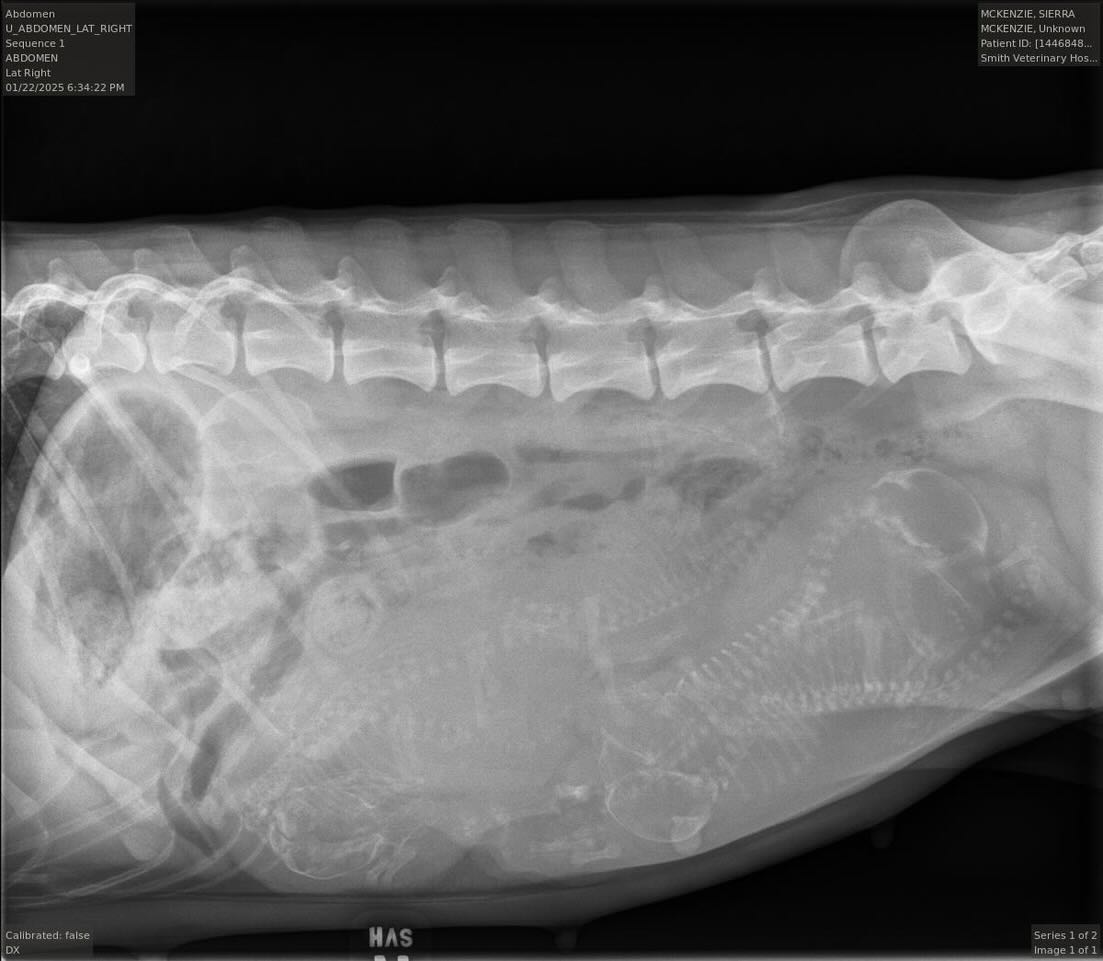

January 22, 2025 Xray at Smith Veterinary Hospital, Santa Fe, New Mexico 5 Puppies Expected!!!!!